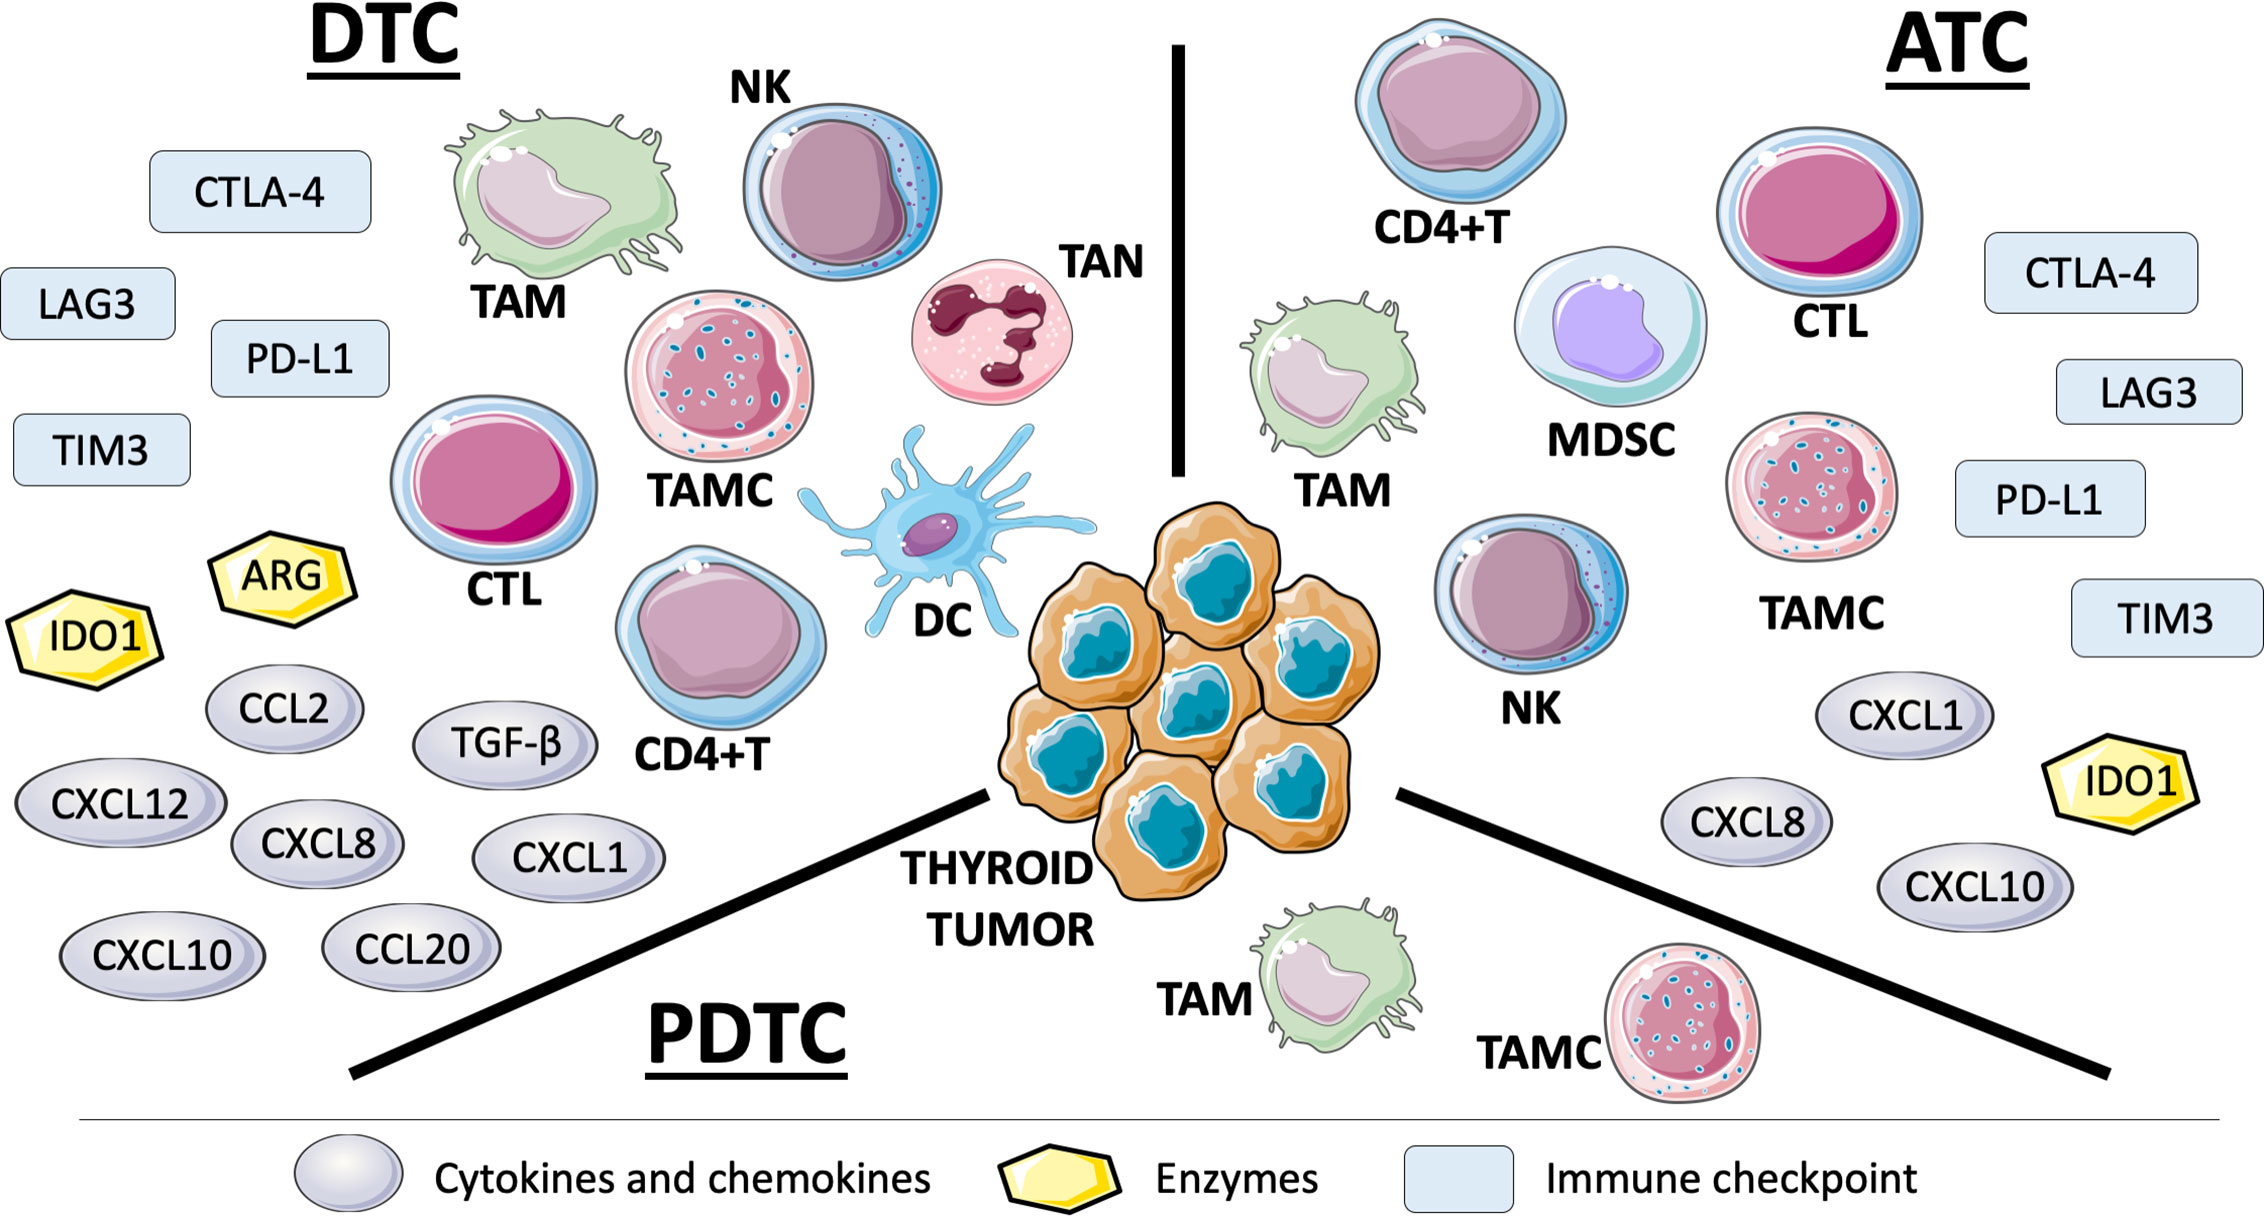

Frontiers Immune Landscape Of Thyroid Cancers New Insights